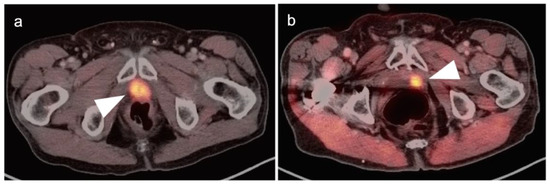

3.1. Prostate Cancer